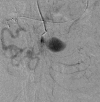

Visceral artery aneurysms are rare, with a 25% rupture risk and an associated 70% mortality. A 55-year-old woman with progressive epigastric pain was found to have multiple large superior mesenteric artery (SMA), branch, and gastroduodenal artery aneurysms along with an occluded celiac artery trunk with hepatic flow dependent on the aneurysm branch. Management included antegrade aortohepatic artery bypass with gastroduodenal artery ligation, followed by SMA stenting and aneurysm coiling. This case is novel, given the diffuse pattern and rarity of SMA and branch aneurysms. This hybrid surgical management highlights innovative strategies to minimize morbidity without compromising definitive treatment of complex visceral artery aneurysms.